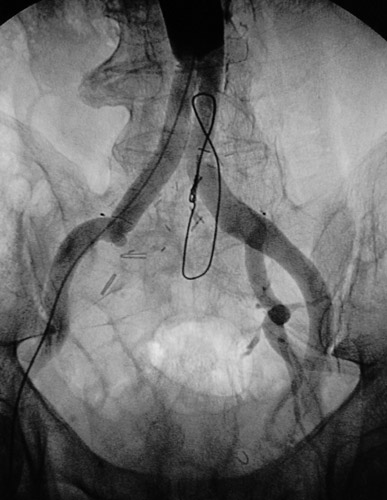

These aortogram views above and below demonstrate a right internal iliac artery occlusion in a patient who has had an aorto-biiliac arterial graft procedure.